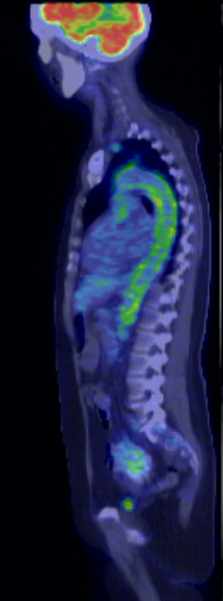

The greatest precision of image registration is achievable if the patient experiences minimal motion differences (the patient lies in the same position and imaging takes place almost at the same time) during both examinations. These requirements are met in hybrid imaging methods, with the implementation of the so called hardware registration. PET-CT, SPECT-CT or the newly emerging PET-MR examinations are all able to utilize hardware registration. The integrated PET/SPECT-CT method represents the latest technical developments of both PET and CT scanners, combined in one machine. It is capable to represent structural and metabolic information simultaneously and identically. The machine’s PET/SPECT and CT components are aligned along the common axial axis, and as the patient table moves along their longitudinal axis, the two examinations are carried out only minutes apart from each other, minimizing any movement or change in the patient’s position. During evaluation the identical slices of CT and PET can be matched with each other and they can be analyzed independently or represented in a fusion image. (Figure 1.)

1. Fusion images; FDG PET-CT, transversal and coronal planes. The dominance of certain components (transparency) can be constantly adjusted on the fused image.

Another advantage of hybrid imaging is that CT can be used for the attenuation correction (AC) of the PET images. Photons arriving from deeper lying tissues have a smaller chance of reaching the detector, due to greater scattering and absorption. The decrease in signal intensity is directly proportional with the local tissue densities. Thus, the activity-maps detected by PET and SPECT cameras do not represent real tissue dependent radiopharmaceutical distributions. Real activity distribution maps are only detectable with the knowledge of tissue densities that are calculated from the attenuation corrected maps, registered during the CT examination. For anatomic localization and attenuation correction, it is sufficient to take a non-diagnostic quality, low-dose CT scan.